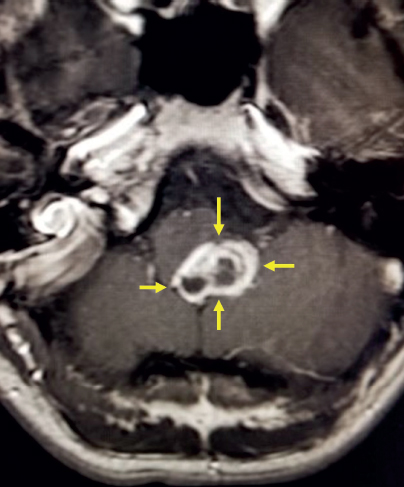

A white colored blob is shown the center of the image. It is highlighted by four yellow arrows on each side. There are two dark gray circular structures beneath the white blob. Additional structures are shown with a very light gray outline surrounding them.

FIGURE 5.1 An MRI of glioblastoma multiforme. Axial post-contrast image demonstrates irregularly enhancing mass in the posterior aspect of the left pons extending to the fourth ventricle that appears bright after being injected with IV contrast (yellow arrows).